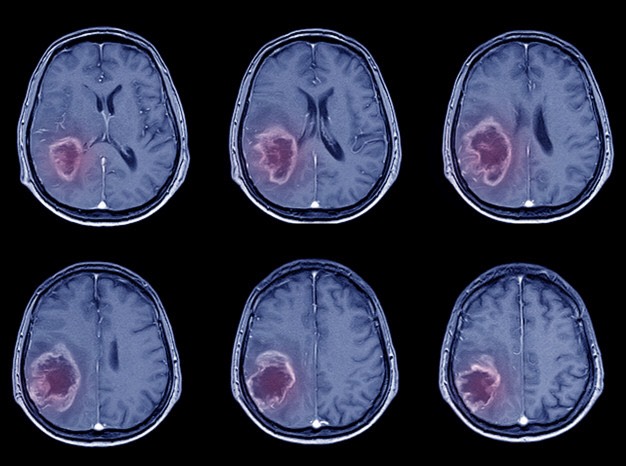

เนื้องอกสมอง คือ การเกิดก้อนเนื้องอกภายในกระโหลกศีรษะ สามารถเกิดได้จากเซลล์ประสาทในสมองแบ่งตัวผิดปกติ หรือเนื้องอกสมองที่เกิดจากการแพร่กระจายของเซลล์มะเร็งในร่างกายเข้าสู่ระบบประสาทในสมองได้

เซลล์มะเร็งจากส่วนต่างๆของร่างกายจะแพร่กระจายจากอวัยวะต้นกำเนิดเซลล์มะเร็ง โดยแพร่กระจายไปทางกระแสเลือดและระบบน้ำเหลือง มักพบในตำแหน่งของเปลือกสมองใหญ่ อยู่ทางด้านนอก(Cerebral cortex) เป็นตำแหน่งที่มีเซลล์มีหลอดเลือดมาเลี้ยงเป็นจำนวนมาก สมองน้อย(Cerebellum) และก้านสมอง(Brain stem) ตามลำดับ